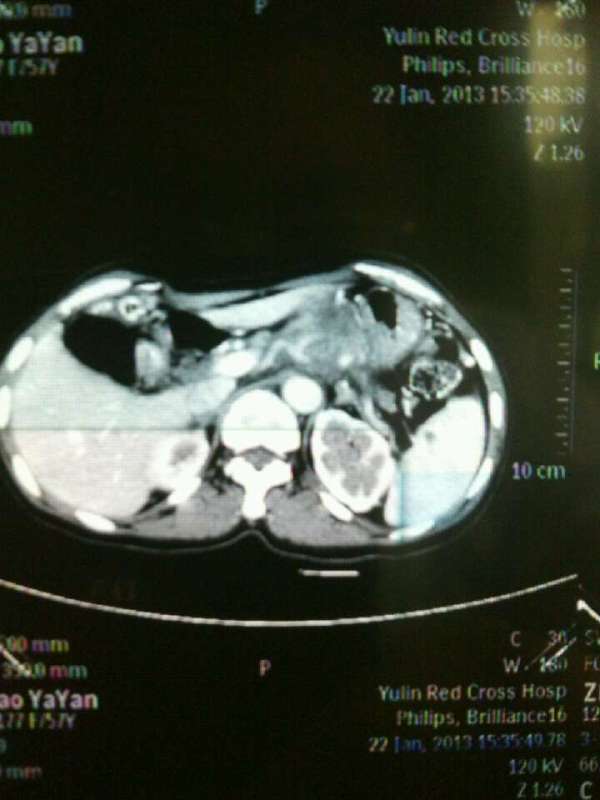

春节刚过,喜庆气氛尚未散去,来自广西平南的赵大妈却无法享受节日的欢乐。因为手术的原因,她已经在我院肝胆肠外科的病床上躺了两个星期了,现...